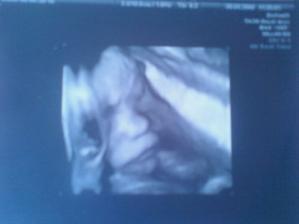

Nasa zubrienka

Pan Boh nam pozehnal malu zubrienku. Velmi sa z nej tesime a modlime sa aby, ked raz vyrastie v nase babo, bolo zdrave a krasne.